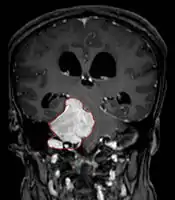

• MRI

• Preferred imaging because it can show dural origin

• Dural tail sign seen in about two-thirds: characteristic marginal thickening that tapers peripherally along the dura

• Isointense on T1, hyperintense (usually homogeneously) on T2, strong enhancement with IV contrast